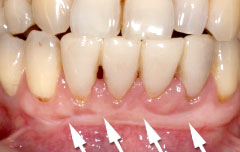

| 歯茎にプラーク(歯垢着が)と歯石の沈認められます。歯肉が腫れ、出血がありました。 | 歯科衛生士の治療と、ブラッシング技術の向上により、歯茎が引き締まり健康的な状態になりました。 | |